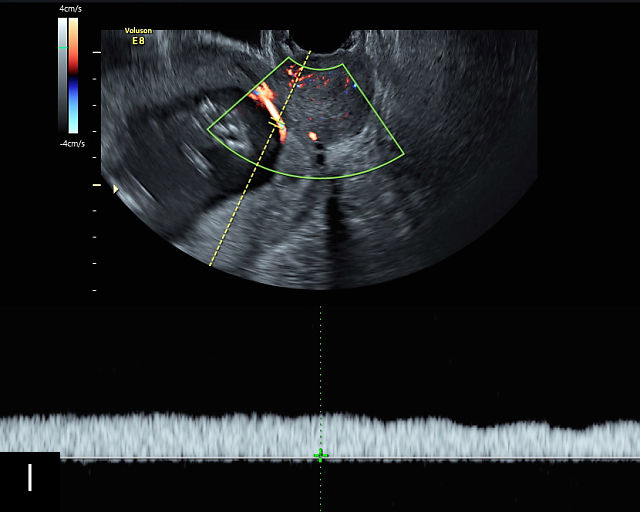

Vasa previa

Vasa previa refers to unprotected fetal vessels running through the membranes over the cervix.30,50,252,253 These vessels often rupture when the membranes rupture during labor or in late pregnancy, resulting in fetal hemorrhage and often exsanguination.252 As a result, this condition is associated with high perinatal mortality.35,252 A large study found a 56% perinatal mortality when vasa previa was not diagnosed prenatally.35 Prenatal diagnosis with ultrasound and cesarean delivery before labor or rupture of the membranes prevents this high perinatal mortality.254,255,256 Risk factors for vasa previa include second-trimester placenta previa or low-lying placenta, velamentous cord insertion, pregnancy resulting from in-vitro fertilization, multifetal gestation and placenta with accessory lobe.30,36,50,257,258,259,260,261

There are three types of vasa previa.30,262 In Type 1, the cord inserts into the membranes rather than the placenta. Unprotected vessels then traverse the membranes over the cervix to insert into the placenta (Figure 21a; Video 12). In Type 2, unprotected vessels running through the membranes over the cervix connect the main placental lobe with an accessory lobe (Figure 21b).263 In Type 3, there is generally a normal placental cord insertion, and unprotected vessels exit one placental edge, run through the membranes over the cervix and then boomerang to insert into the placental edge at another site (Figure 21c).25,28,29,264 Regardless of the type, all these expose the fetus to the same risks.

21